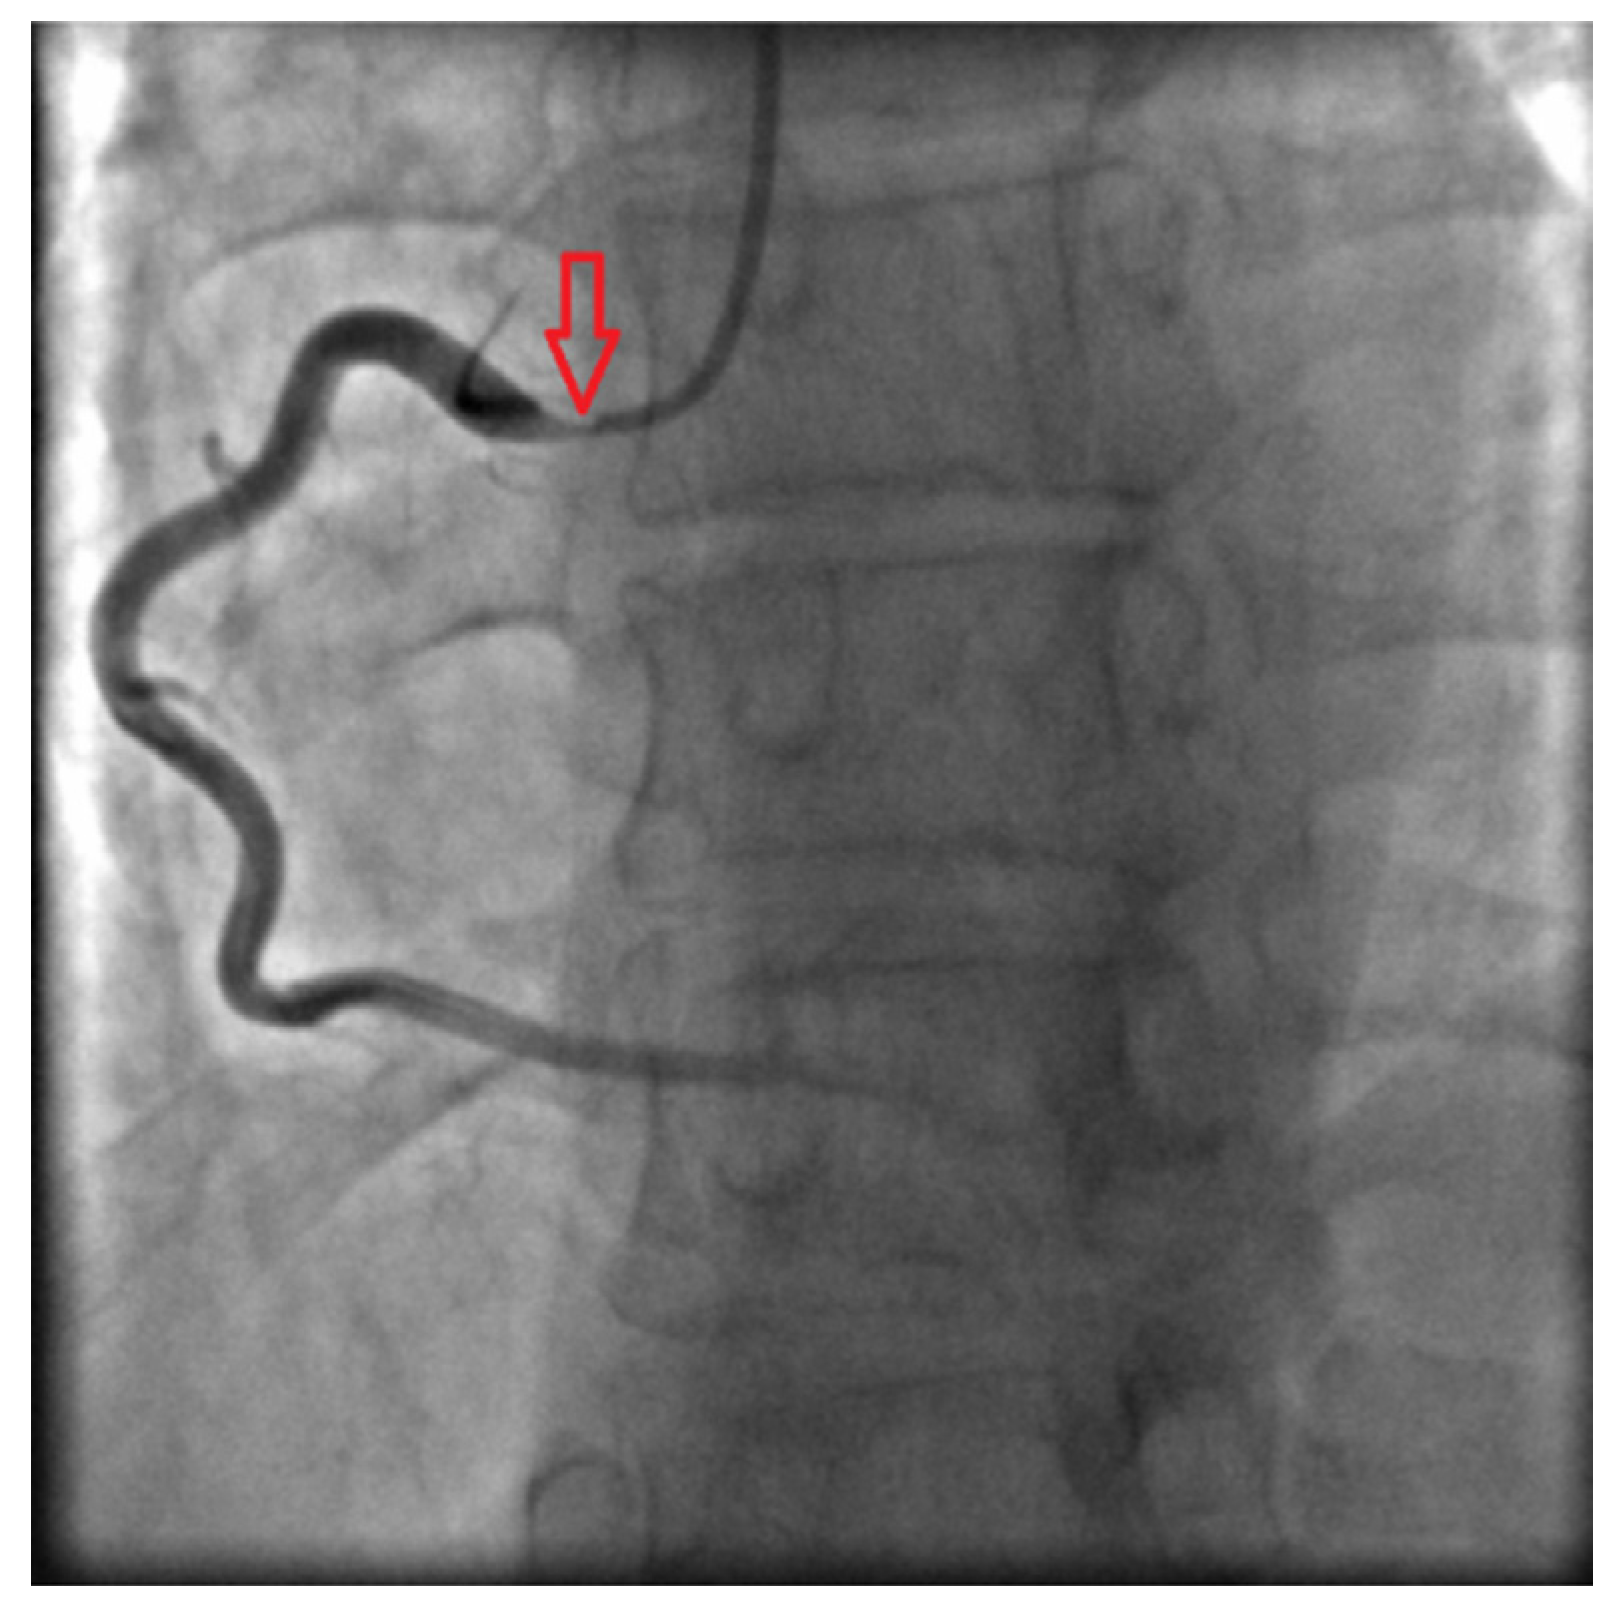

Coronary angiography clarified causes of chest pain: subocclusions of right and left main coronary arteries were found (Fig. 3 and Fig. 4).

Fig. 4. - Right coronary angiogram shows critical ostial stenosis.